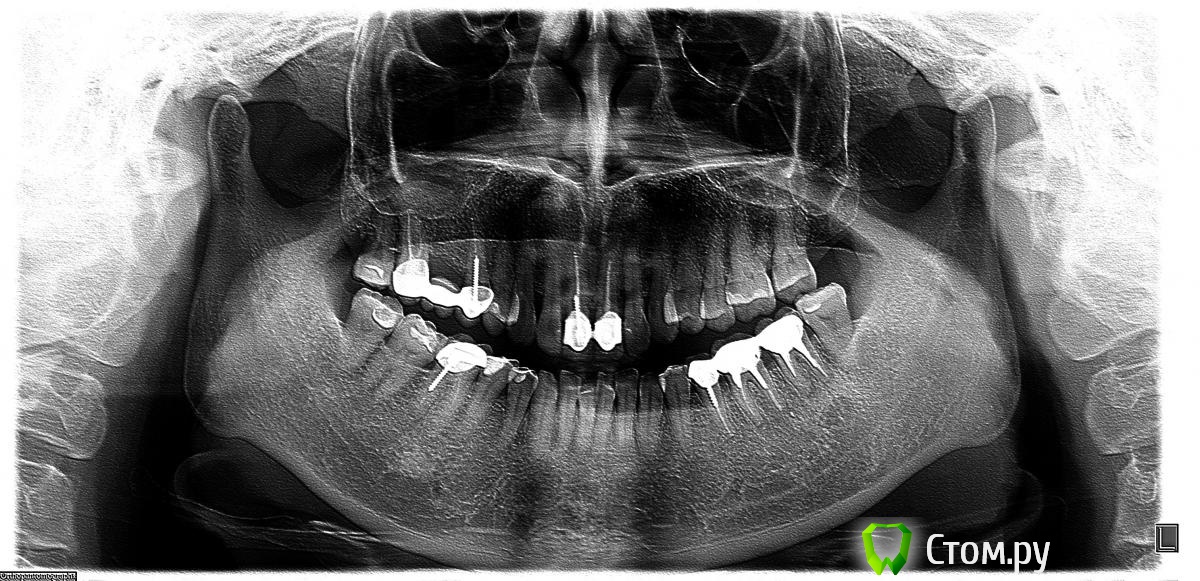

Клара Захаровна Опубликовано 27 февраля, 2014 Автор Поделиться Опубликовано 27 февраля, 2014 Вот снимки до лечения и после. Увидела яркие пятнышки в конце корня, как-будто пломбировочный материал забит, это нормально? У меня после пломбировки 5 и 6 зубов была температура 37,6 почти сутки. Врач сказал, что это реакция организма на пломбировочный материал. После моих жалоб оставшийся корень 7 зуба эндодонтист забивала уже не так долго и усердно. Вчера ортопед снова убеждал взять 8 под коронку, мотивировал еще и тем, что сверху 8-антагониста нет, расстояние между зубом и верхней десной осталось очень маленькое, надо заставить эту 8 работать. Т.е. при коронке на 5-6-7-8 нагрузка будет распределяться равномерно. http://i023.radikal.ru/1402/0b/c34f9f0ec0da.jpg http://s017.radikal.ru/i425/1402/b0/ed61bb36ed7b.jpg Ссылка на комментарий

red_butler Опубликовано 27 февраля, 2014 Поделиться Опубликовано 27 февраля, 2014 Я тоже за удаление. И похоже или корень удален не полностью, или в лунке инородное телоhttp://s019.radikal.ru/i630/1402/6c/50e3ecc04e46.jpg Ссылка на комментарий